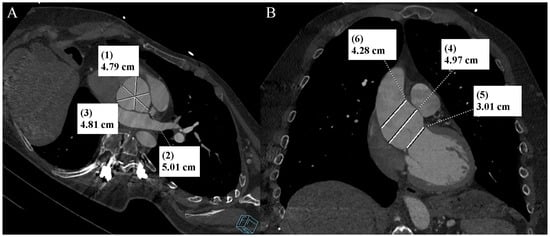

Ehlers–Danlos syndrome (EDS) encompasses a spectrum of heterogeneous, heritable disorders affecting connective tissue. According to the 2017 international classification of EDS, there are 13 subtypes. A rare 14th subtype was found in 2018. Each subtype has unique aspects, and a genetic cause has been identified in all subtypes except hypermobile EDS [1]. Clinical manifestations arise from the pervasive fragility and weakness of the soft connective tissue. Apart from manifestations in the skin, ligaments, joint and internal organs, there are subtypes of EDS which affect blood vessels and cardiac valves. These subtypes confer a higher risk of cardiac valve insufficiency, aneurysms, dissections, or ruptures of arteries, including coronary ruptures [2]. The estimated prevalence of EDS approximates 194.2 cases per 100,000 individuals [3]. Here, we present a case of a 34-year-old man with normal body weight, with hypermobile EDS, type 2 diabetes mellitus, chest deformity, aortic valve regurgitation, and aortic bulb aneurysm characterized by an axial diameter measuring approximately 5 cm (Figure 1). The patient had severe rotational scoliosis of the Th-L spine, with a significant deepening of the thoracic kyphosis and lumbar lordosis. There was a decrease in the AP dimension of the chest, a deformation of the ribs with a decrease in the width of some intercostal spaces, and a secondary widening of the width of other intercostal spaces. The patient underwent elective spine surgery to correct severe rotational scoliosis of the T-L spine. After postoperative rehabilitation, the patient underwent a thorough assessment of eligibility for aortic bulb aneurysm and aortic valve replacement surgeries. Consequently, a coronary computed tomography angiography (CCTA) was performed five months after the spinal surgical intervention. The CCTA revealed an absence of the left main (LM) and the right coronary artery (RCA) dominance. Significantly, the left circumflex artery (LCx) exhibited an ectopic origin from the right sinus of the valsalva, demonstrating a retroaortic course in the proximal segment and a typical course in the distal segments (Figure 2). Furthermore, the presence of a coronary–pulmonary arterial fistula (CPAF) in the CCTA was visualized. A vessel with an approximate diameter of 0.3 cm originated from the right sinus of the valsalva and progressed anteriorly and then towards the left, traversing anteriorly to the right ventricular outflow tract. Thereafter, this vessel was visible to the left of the main pulmonary artery, ultimately divided into multiple narrow segmentally aneurysmally dilated and tortuous fistula vessels. The fistula vessels showed communication with the proximal segment of the main pulmonary artery (Figure 3). Moreover, the imaging revealed the presence of an additional right pulmonary vein (Figure 4). The CCTA revealed calcifications within the aortic valve. The patient received a qualification card for surgical treatment, was informed about the high surgical risk, and is awaiting the operation.

Figure 1. Thoracic aorta computed tomography angiography. Aortic bulb aneurysm. (A). Multiplanar reconstruction. View parallel to the aortic annulus plane. Subsequent measurements were made between the commissures of the aortic valve leaflets and the midpoints of the aortic valve leaflets. (B). Multiplanar reconstruction. Perpendicular view to the aortic annulus plane in the long axis. The designations (1–6) indicate subsequent measurements: aortic annulus—3.01 cm (5); aortic bulb—4.79 cm (1), 5.01 cm (2), 4.81 cm (3), 4.97 cm (4); sinotubular junction—4.28 cm (6).